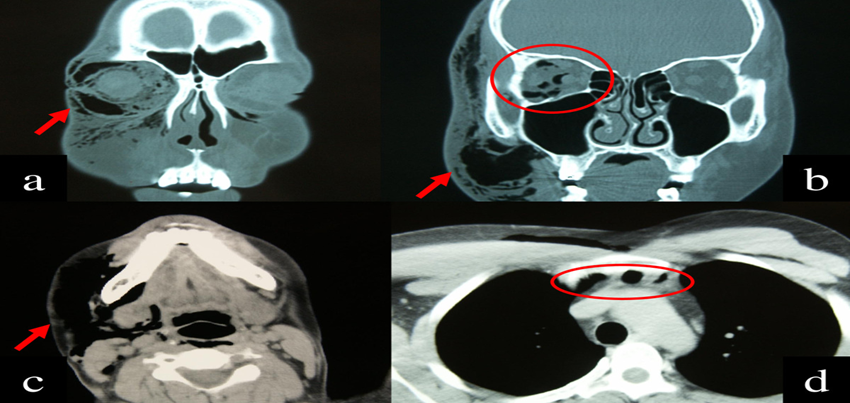

Interpretation of Brain and Orbit CT Scan Results:

Interpretation of brain and orbit CT scan results requires expertise in radiology and neurology or ophthalmology to accurately analyze imaging findings. Radiologists assess various parameters, including brain parenchyma, ventricular size, skull integrity, orbital structures, and soft tissue abnormalities. They identify any abnormalities or pathology present and provide a detailed report for further evaluation and management.